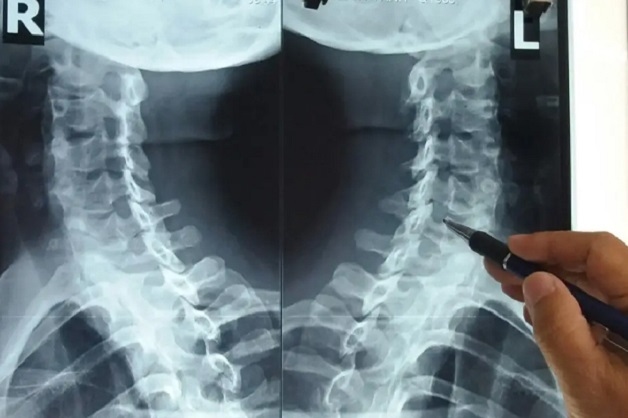

Chụp x quang là một phương pháp chẩn đoán hình ảnh phổ biến tại các bệnh viện hiện nay. Đây là chìa khóa để xác định, chẩn đoán, tầm soát một số bệnh lý trong cơ thể mà mắt thường không nhìn thấy được.

Chụp X quang được ứng dụng trong chẩn đoán một số bệnh lý như:

Chụp x quang là phương pháp chẩn đoán, tầm soát một số bệnh lý trong cơ thể mà mắt thường không nhìn thấy được.